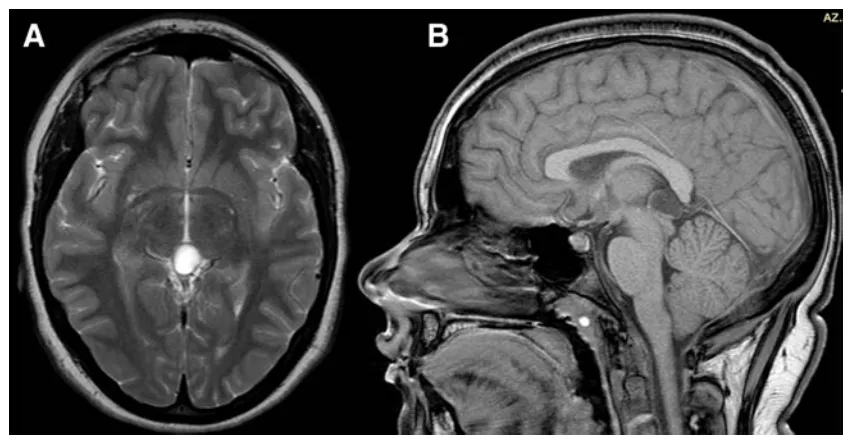

谁也想不到,宝贝女儿偶尔喊头痛、怕光、看不清,原因竟是脑子里面生病了。MRI检查显示豆豆的松果体区存在一个直径13毫米的囊肿(图1)。

图1首次脑MRI,显示一枚直径13 mm的松果体囊肿(见箭头)。